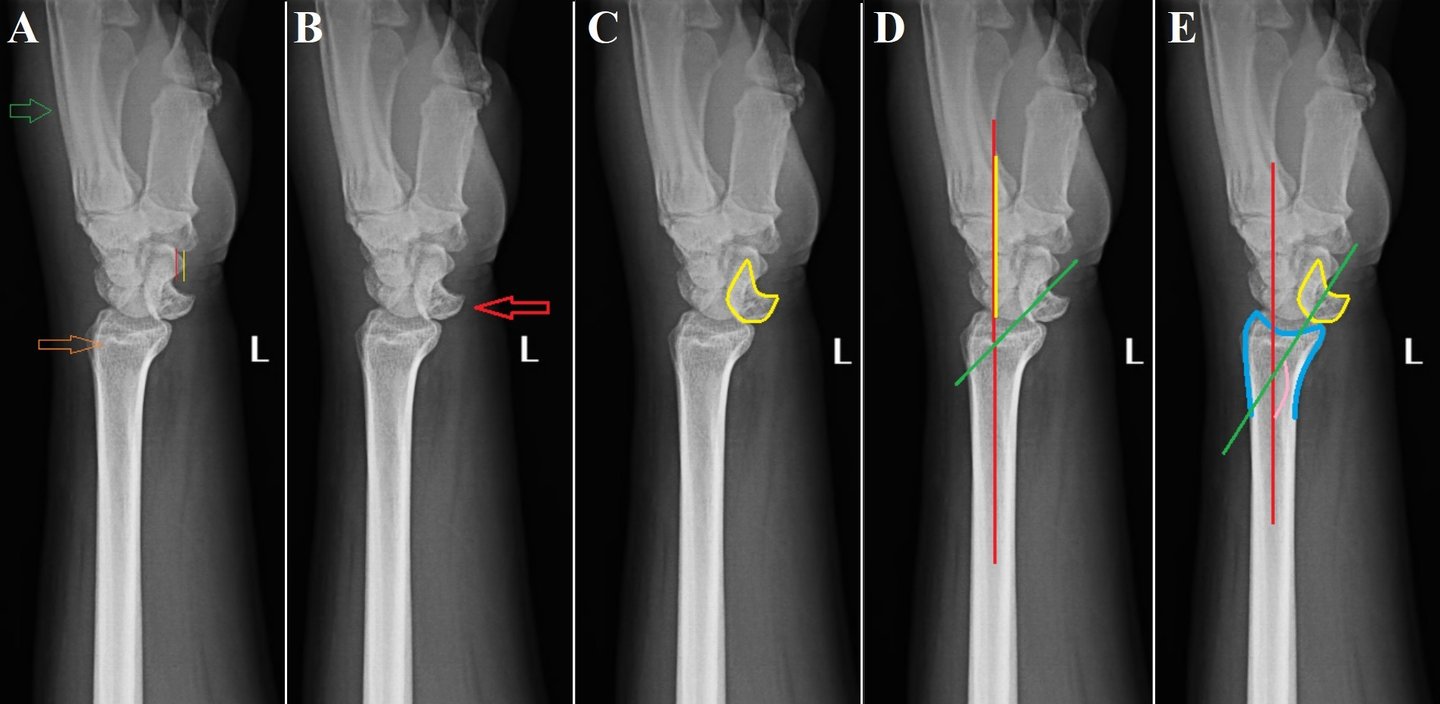

Isolated lunate dislocation

Perilunate dislocations are rare traumatic injuries of the wrist. They are classified according to the Mayfield classification system. Among these, lunate dislocations represent only the type IV injury, which are among the most unstable. Isolated lunate dislocations are often unrecognised as the rest of the carpus remains aligned. The rate of incorrect diagnosis is reported to be as high as 25%. Neglected lunate dislocations can lead to median nerve dysfunction, carpal instability, avascular necrosis of lunate and arthritis. Careful analysis of radiographs is required for diagnosis, indicated by disruptions of Gilula’s arc, lunocapitate overlap on posteroanterior radiographs and spilling teacup sign, increased radiolunate angle on lateral radiographs.